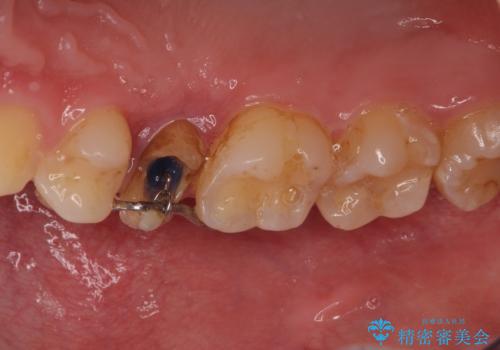

右上の被せものを除去したところ、中で歯が割れていたため、部分矯正で引っ張り出すことになりました。

歯を引っ張り出したり、歯肉の手術の経過待ちの間に、患者様のご希望で他の歯の虫歯治療も行いました。

・約3か月ほど引っ張り出します。

・両どなりの歯に一時的にワイヤーを接着します。

・十分に引っ張り出した後、歯肉の手術が必要となります。